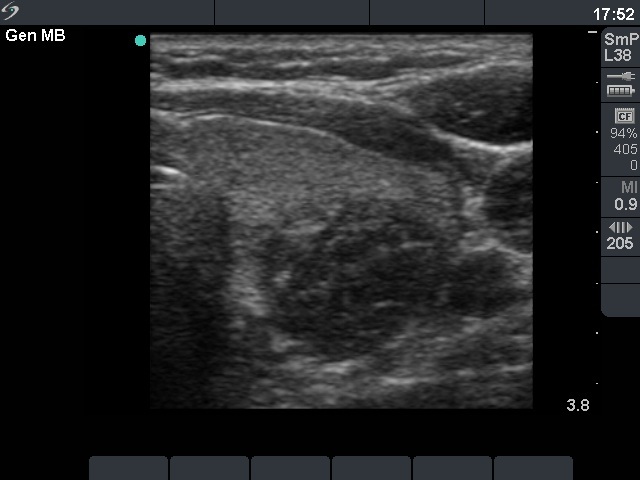

Second row: 6 weeks after the last session. The dimensions of the nodule were 15x18x18 mm (width x depth x length).

Third row: 19 months after sclerotherapy. The dimensions of the nodule were 15x14x19 mm (width x depth x length).